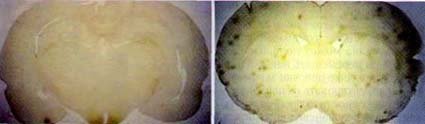

Рис. 1. Мозг крысы, которая не была облучена (а) и крысы, которую регулярно облучали (б), темные точки – это пораженные участки.

Опыты, которые проводились над животными разного возраста, показали, что электромагнитное поле очень сильно влияет на развивающийся организм. При использовании мобильного телефона происходит воздействие электромагнитного поля на головной мозг (рис. 2).

Рис. 2. Результаты проникновения ЭМВ в голову взрослого человека (а), 10-ти летнего ребенка (б), и 5-ти летнего ребенка

Поглощение ЭМ энергии в голове ребенка намного выше, чем у взрослого человека, потому что у ребенка меньше размер головы, кости черепа более тонкие, мозговая ткань имеет большую проводимость. Детский организм более чувствителен к ЭМ полю, чем взрослый, мозг имеет большую склонность к накоплению неблагоприятных реакций при повторных облучениях ЭМ полем.